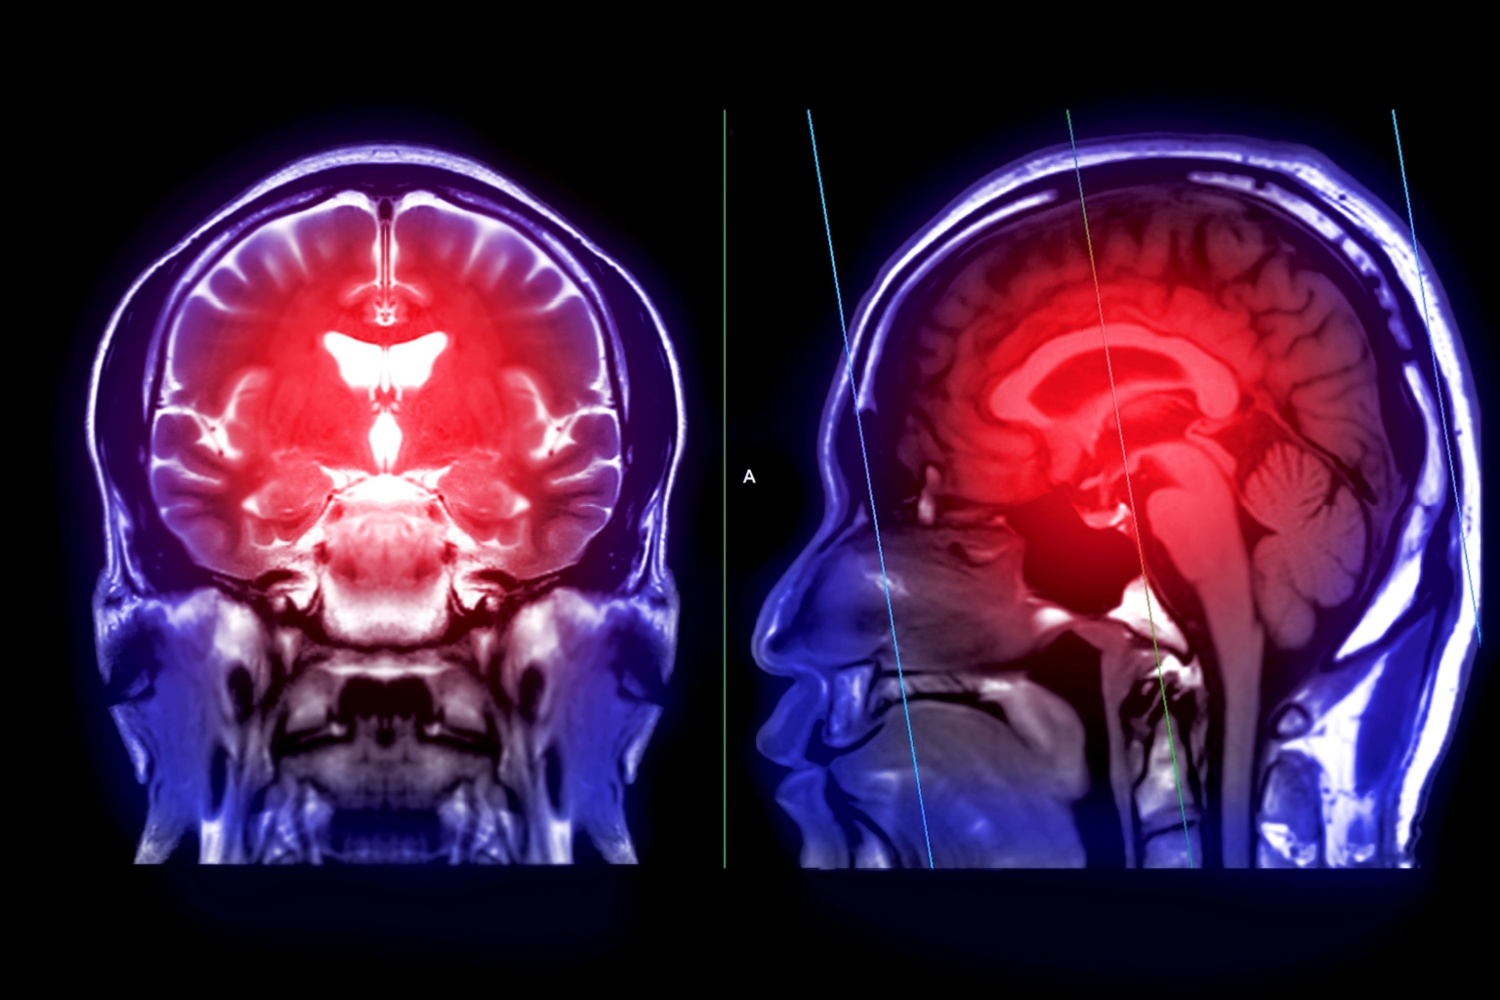

Çoğu durumda, bir beyin kisti bilgisayarlı tomografi (BT) veya manyetik rezonans görüntüleme (MRG) taramalarıyla teşhis edilir. Ayrıca bir radyoloji teknisyeni veya radyolog genellikle bu taramaları yorumlar. Bu tür bir tarama, doktorun kafatası içindeki beyin dokusunu ve çevresini görüntülemesini sağlar. Bu testler ayrıca beyindeki her tür kist veya tümörün yerini ve büyüklüğünü belirlemeye yardımcı olabilir.